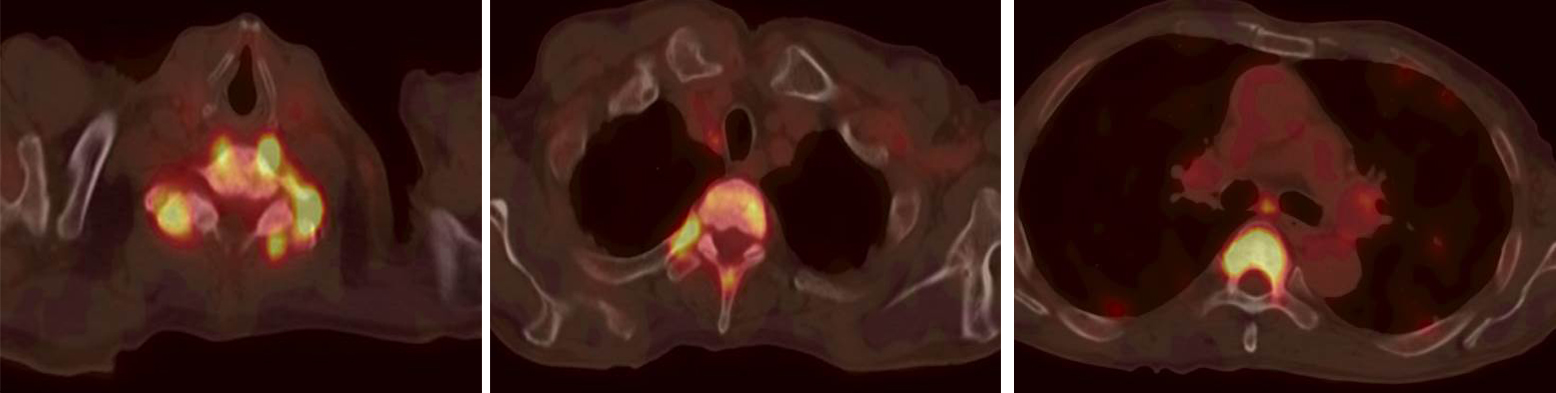

檢查后發(fā)現(xiàn)郭老伯的胰腺體尾部增大,放射性攝取異常增高,SUVmax 9.5。雙肺內(nèi)彌漫分布大小不等結(jié)節(jié),放射性攝取增高,SUVmax 6.1。全身多發(fā)骨質(zhì)破壞,放射性攝取增高,SUVmax 8.5。雙側(cè)鎖骨區(qū)、網(wǎng)膜囊、腹膜后及右側(cè)膈腳后間隙多發(fā)增大淋巴結(jié),放射性攝取增高,SUVmax 12.1。

影像科醫(yī)生考慮為:胰腺癌并雙肺轉(zhuǎn)移,多發(fā)骨轉(zhuǎn)移,多發(fā)淋巴結(jié)轉(zhuǎn)移

多發(fā)骨骼轉(zhuǎn)移灶